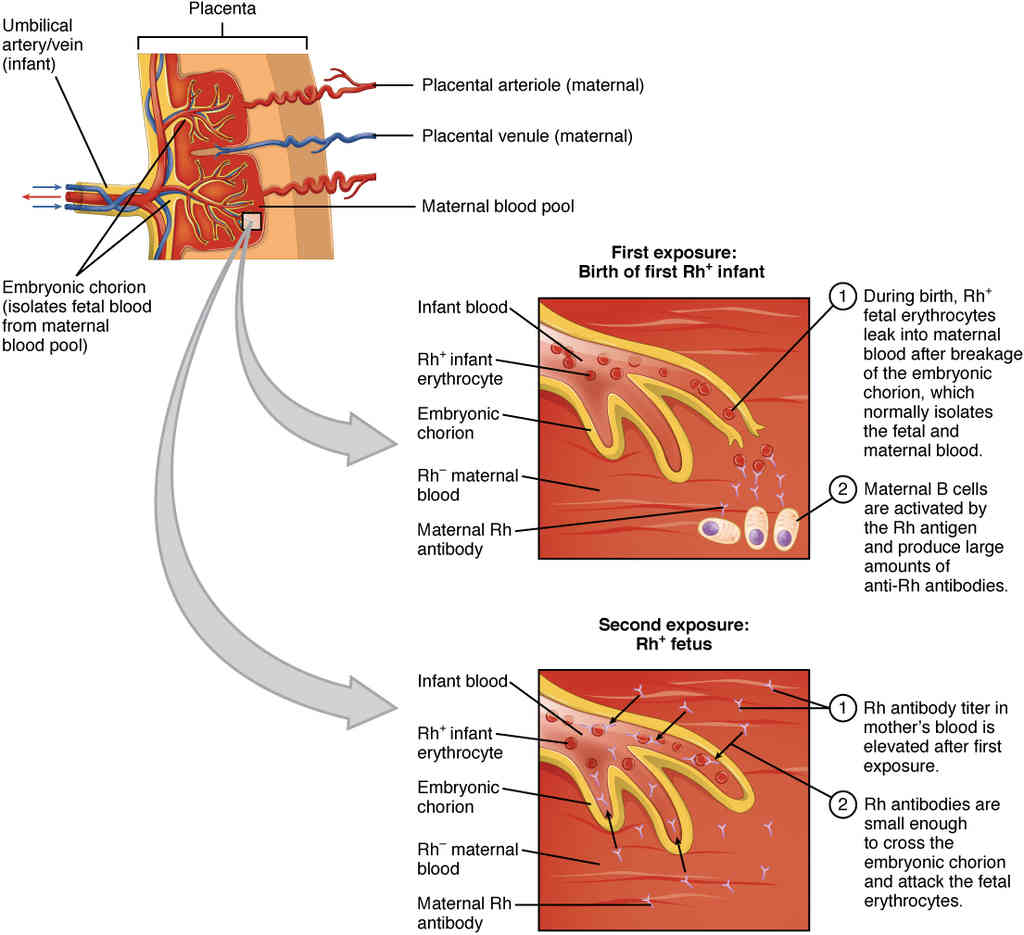

This page is under construction. For now, it is just a resource of the images found in the OpenStax Anatomy and Physiology Handbook. It wil slowly change into a revision tool. Each slide has a number. Use this to refer to the slide. When completed, it will have an unlabelled section, with labelled slides in parallel. On the unlabelled slides, write your answer and use the labelled slide to assess yourself. Keep track by also noting the number on each slide. Improvement at each attempt is important, more so than full marks on a first attempt.